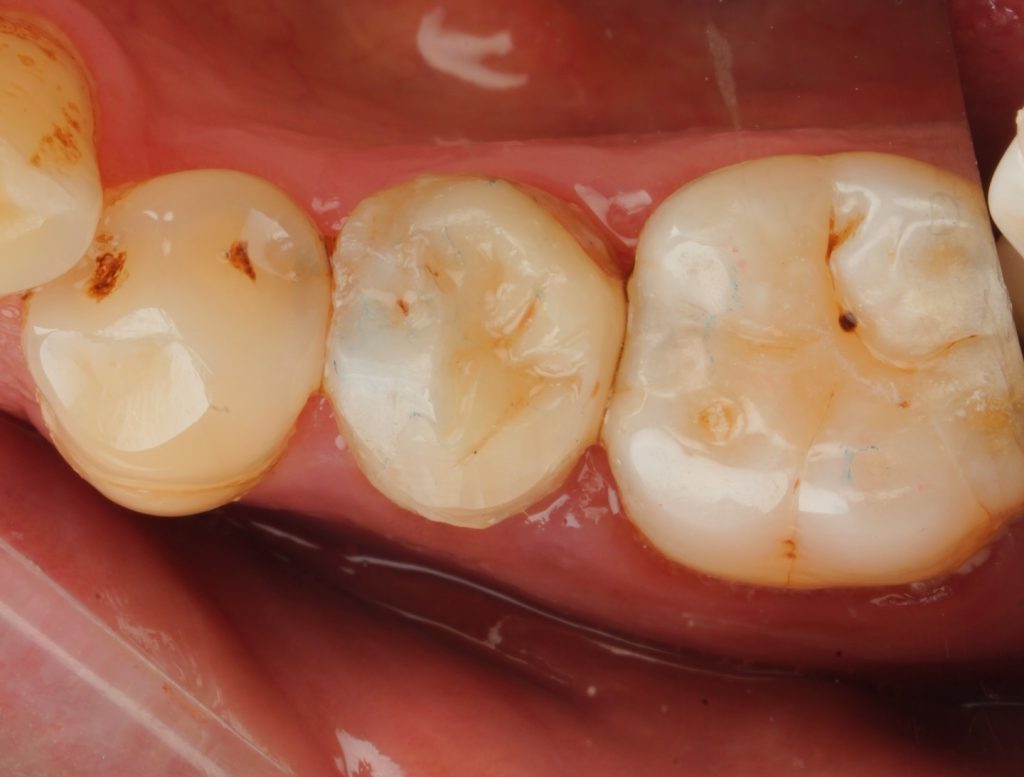

Rubber-dam isolation was achieved (Fig 2). The temporary filling and superficial debris were removed, access refined, and obturation integrity evaluated. Minor GP adjustment was done to create a flat pulpal floor for composite adaptation.

A 1 mm substructure of GC EverX Flow was placed as a dentin substitute (Fig 4). The short-fiber composite reinforced the internal core, reduced stress concentration, and improved load distribution beneath the cusp coverage.

- Fig 2: Rubber-dam isolation and access refinement.

- Fig 4: Base reinforcement with GC EverX Flow.

- Fig 5: Adhesive protocol and Class II build-up with sectional matrix.